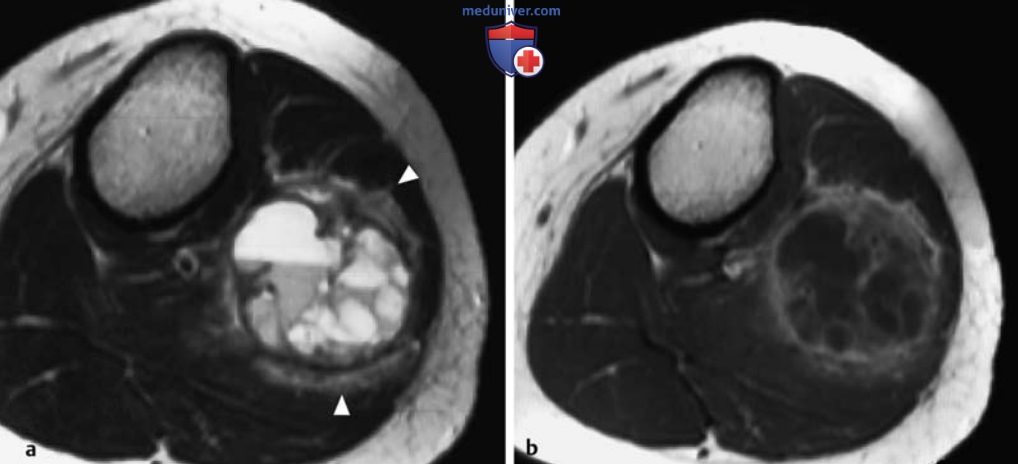

МРТ доброкачественных опухолей костей и опухолеподобных поражений

Рисунок 10. а, b Аневризматическая костная киста проксимального отдела малоберцовой кости.

а Т2в-SЕ-изображение в аксиальной плоскости.

b Т1в-SЕ-изображение после контрастирования.

Определяется кистозное поражение с экспансивным ростом, множественными септами, уровнями жидкости и гипоинтенсивным окаймлением на Т2в-изображениях. Отмечается интенсивное усиление сигнала от стенки кисты на Т1в-изображениях после контрастирования. Заметьте отек окружающей мышечной ткани (головки стрелок) и значительное вздутие кости.